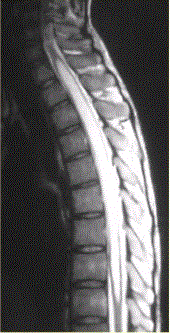

问题 患者女,45岁,胸部不适。影像学检查结果如下图所示。 关于成血管细胞瘤,正确的是

选项 A.脊髓内肿瘤 B.X线检查无阳性发现 C.明显增强的血管性壁结节对定性诊断价值 D.可多发,并伴发von-Hippel-lindau综合征 E.肿瘤上下或肿瘤内区域内见葡状生长的流空信号,可以确诊 F.发病率较低